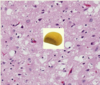

33 yo HIV+ F w/ low grade fever and HA x3 mo

- exam: cognitively slow, stiff neck

- LP shows 200 WBC

- CSF stain attached

(a) Dx

(b) Preferred Tx

(a) Cryptococcus neoformans = yeast that causes meningitis in immunocompromised, typically presents as lung infxn

(b) IV Amphotericin, then fluconazole